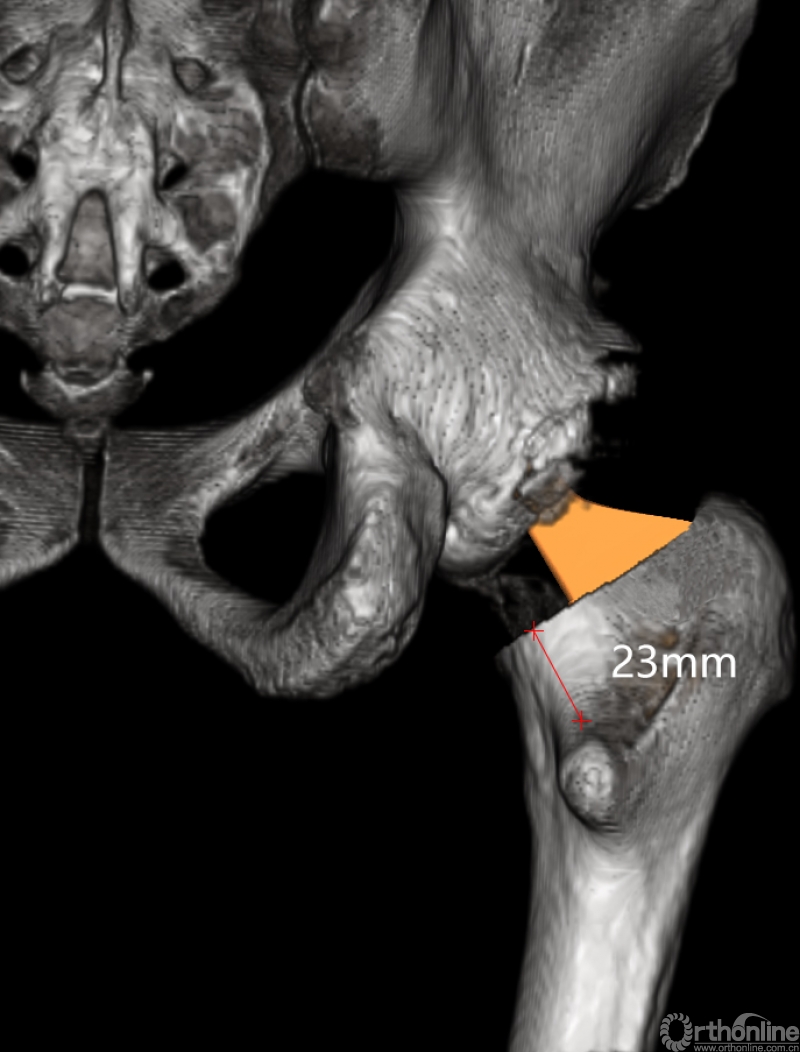

最后,AI HIP系统根据患侧股骨颈干角、偏心距偏大的特殊情况,智能选择使用高偏高颈干角假体,对下肢等长和等偏心距重建做出了精准设计。根据系统预测结果,术中使用54mm Pinnalce髋臼杯、12号CORAIL高偏股骨柄、36mm 陶瓷股骨头、小转子上23mm截骨,实现髋关节的个体化、精准化重建。